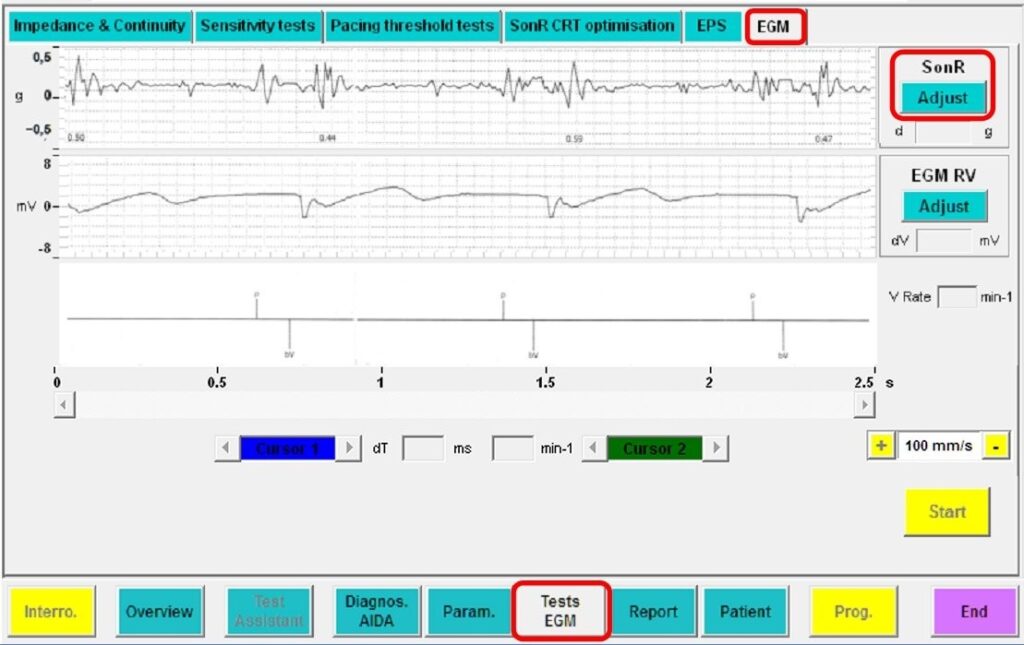

Le SonR CRT-D peut également transmettre des signaux SonR en temps réel par télémétrie.

Inspection en temps réel du signal SonR